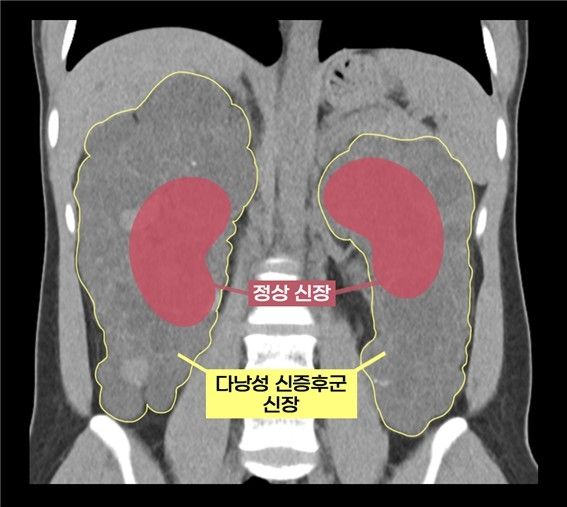

실제 다낭성 신증후군 환자의 신장과 정상 신장 비교 실제 다낭성 신증후군 환자의 신장과 정상 신장 비교

[서울아산병원 제공]

다낭성 신증후군은 신장에 수많은 낭종이 발생해 신장이 최대 축구공 크기만큼 커지는 유전질환으로, 1천 명 중 한 명꼴로 발병한다. 대개 만성 신부전으로 이어진다.